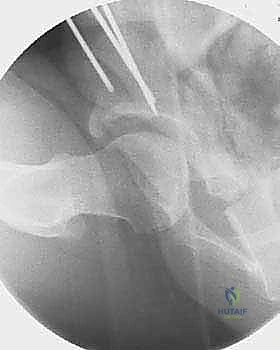

2. سلسلة قطع العظام (The 5 Osteotomies)

يكمن سر نجاح جراحة PAO في إجراء خمسة قطوع عظمية منفصلة حول الحُق، لتحريره بالكامل عن باقي الحوض، مع ترك العمود الخلفي سليماً كدعامة أساسية.

القطع الأول: القطع الإسكي غير المكتمل (Incomplete Ischial Osteotomy)

باستخدام إزميل خاص ذو زاوية (Angled Osteotome)، يتم إجراء قطع في عظم الإسك أسفل الحُق مباشرة (في الأخدود تحت الحُقي). يتم هذا القطع بتوجيه الأشعة السينية (Fluoroscopy) لضمان عدم اختراق المفصل. يحرص الدكتور هطيف على إبعاد العصب الوركي والأوعية السدادية بأمان تام.